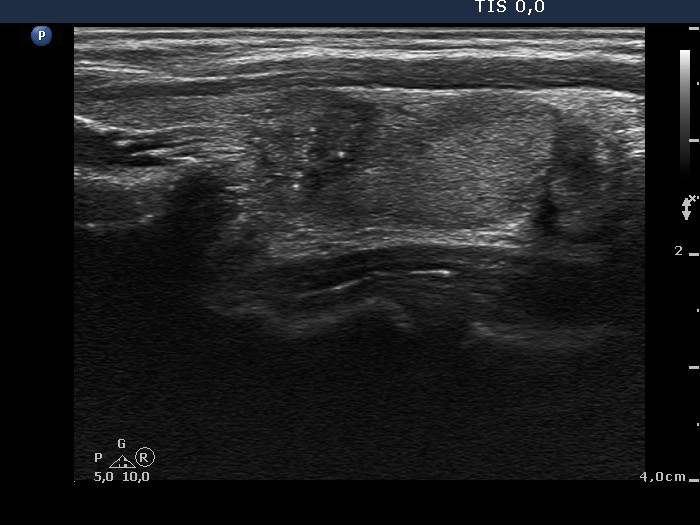

100 consecutive cases of papillary cancer - case 032 (ultrasonographic picture 5)

Middle third of the left lobe, another longitudinal scan. The nodule presents microcalcifications and lobulated margins.